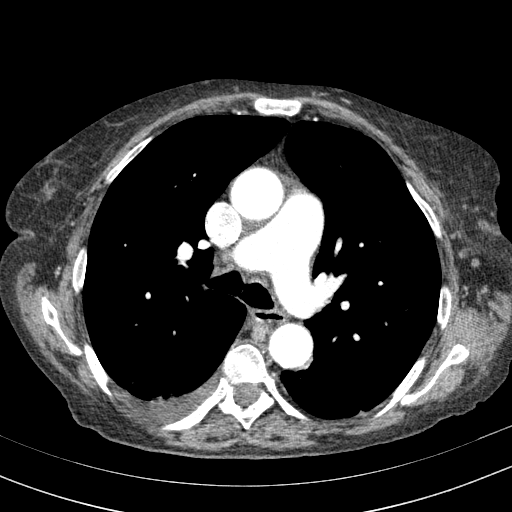

Original VENOUS CT scan

Full window (WL 1023.5, WW 4095 β†’ Low βˆ’1024, High +3071)

Lung window (WL -600, WW 1500 β†’ Low βˆ’1350, High +150)